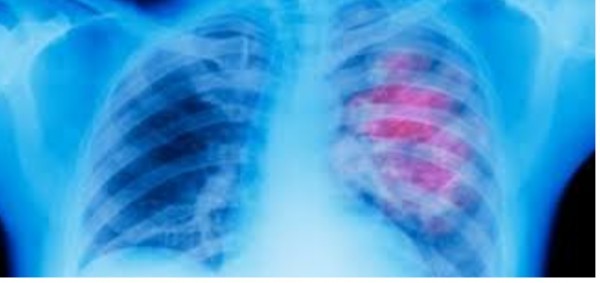

Më 29 korrik 1928 u përdor për herë të parë “mushkëria e hekurt”, siç u quajt ajo, për të ndihmuar njerëzit me probleme të frymëmarrjes.

Aparatura u krijua nga Ira Drinker, mjek në spitalin e universitetit Harvard dhe u instalua në Bellevue të Nju Jorkut, spitali më i madh publik.

Në fillim kjo pajisje dha rezultate të shumë të suksesshme, por fakti është se pacienti që ka nevojë për të duhet të jetë vazhdimisht nën kontrollin e personelit shëndetësor.

Me kalimin e viteve, me përparimin e teknologjisë, u krijuan aparatura shumë më të vogla dhe më të përshtatshme për t’u përdorur, pa pasur nevojë që pacienti të shtrohet në spital, por ai mund ta mbajë atë me vete, në mënyrë që ta ndihmojë në çdo kohë për të normalizuar frymëmarrjen./KP